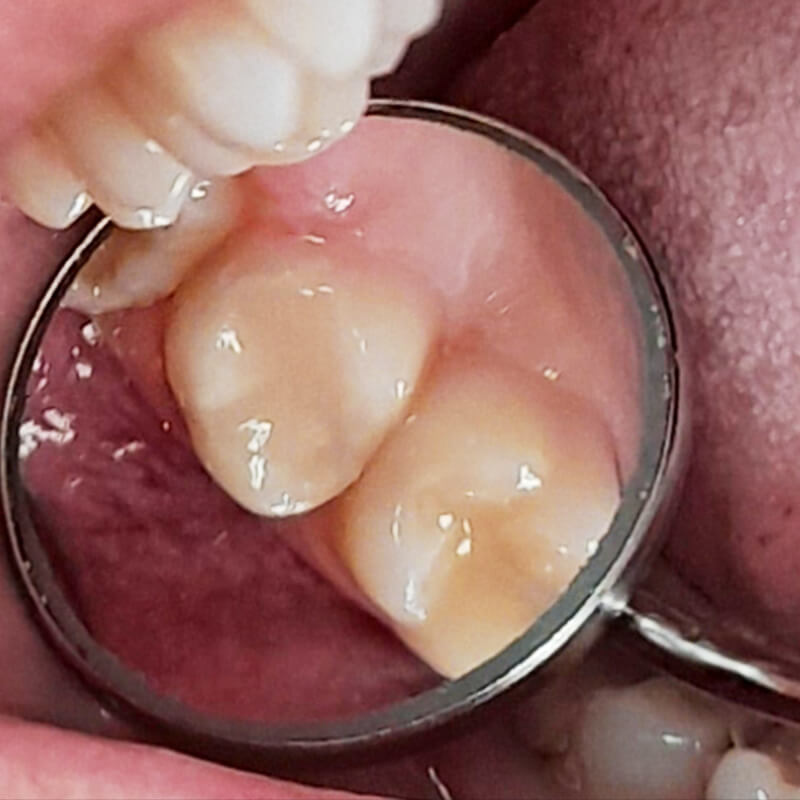

Пациент обратился в «Стоматологию Комфорта» по адресу: Ул.Дыбенко 27 с жалобой на боль от сладкого в левом верхнем зубе. При осмотре, после проведения всех необходимых процедур, врач-стоматолог Луцюк Наталья Владимировна диагностировала кариес дентина зуба 2.6. После этого было принято решение о проведении механической обработки кариозной полости под контролем кариес-маркера и использовании анестезии.

Среднее кариозное поражение дентина расположено ближе к эмали. Такой вид кариеса характеризуется болевой реакцией в ответ на температурные или вкусовые раздражители, она быстро проходит, а промежутки без болевых ощущений продолжительные. Для избежания осложнений вовремя посещайте стоматолога – 2 раза в год или при первых болевых ощущениях.

В ходе лечения врач провёл следующие манипуляции:

- инфильтрационная анестезия;

- механическая обработка полости под контролем кариес-маркера;

- медикаментозная обработка;

- постановка пломбы из композита Estelite.